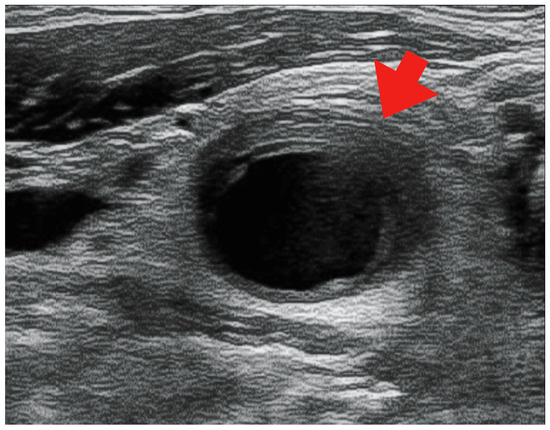

2. Case Presentation